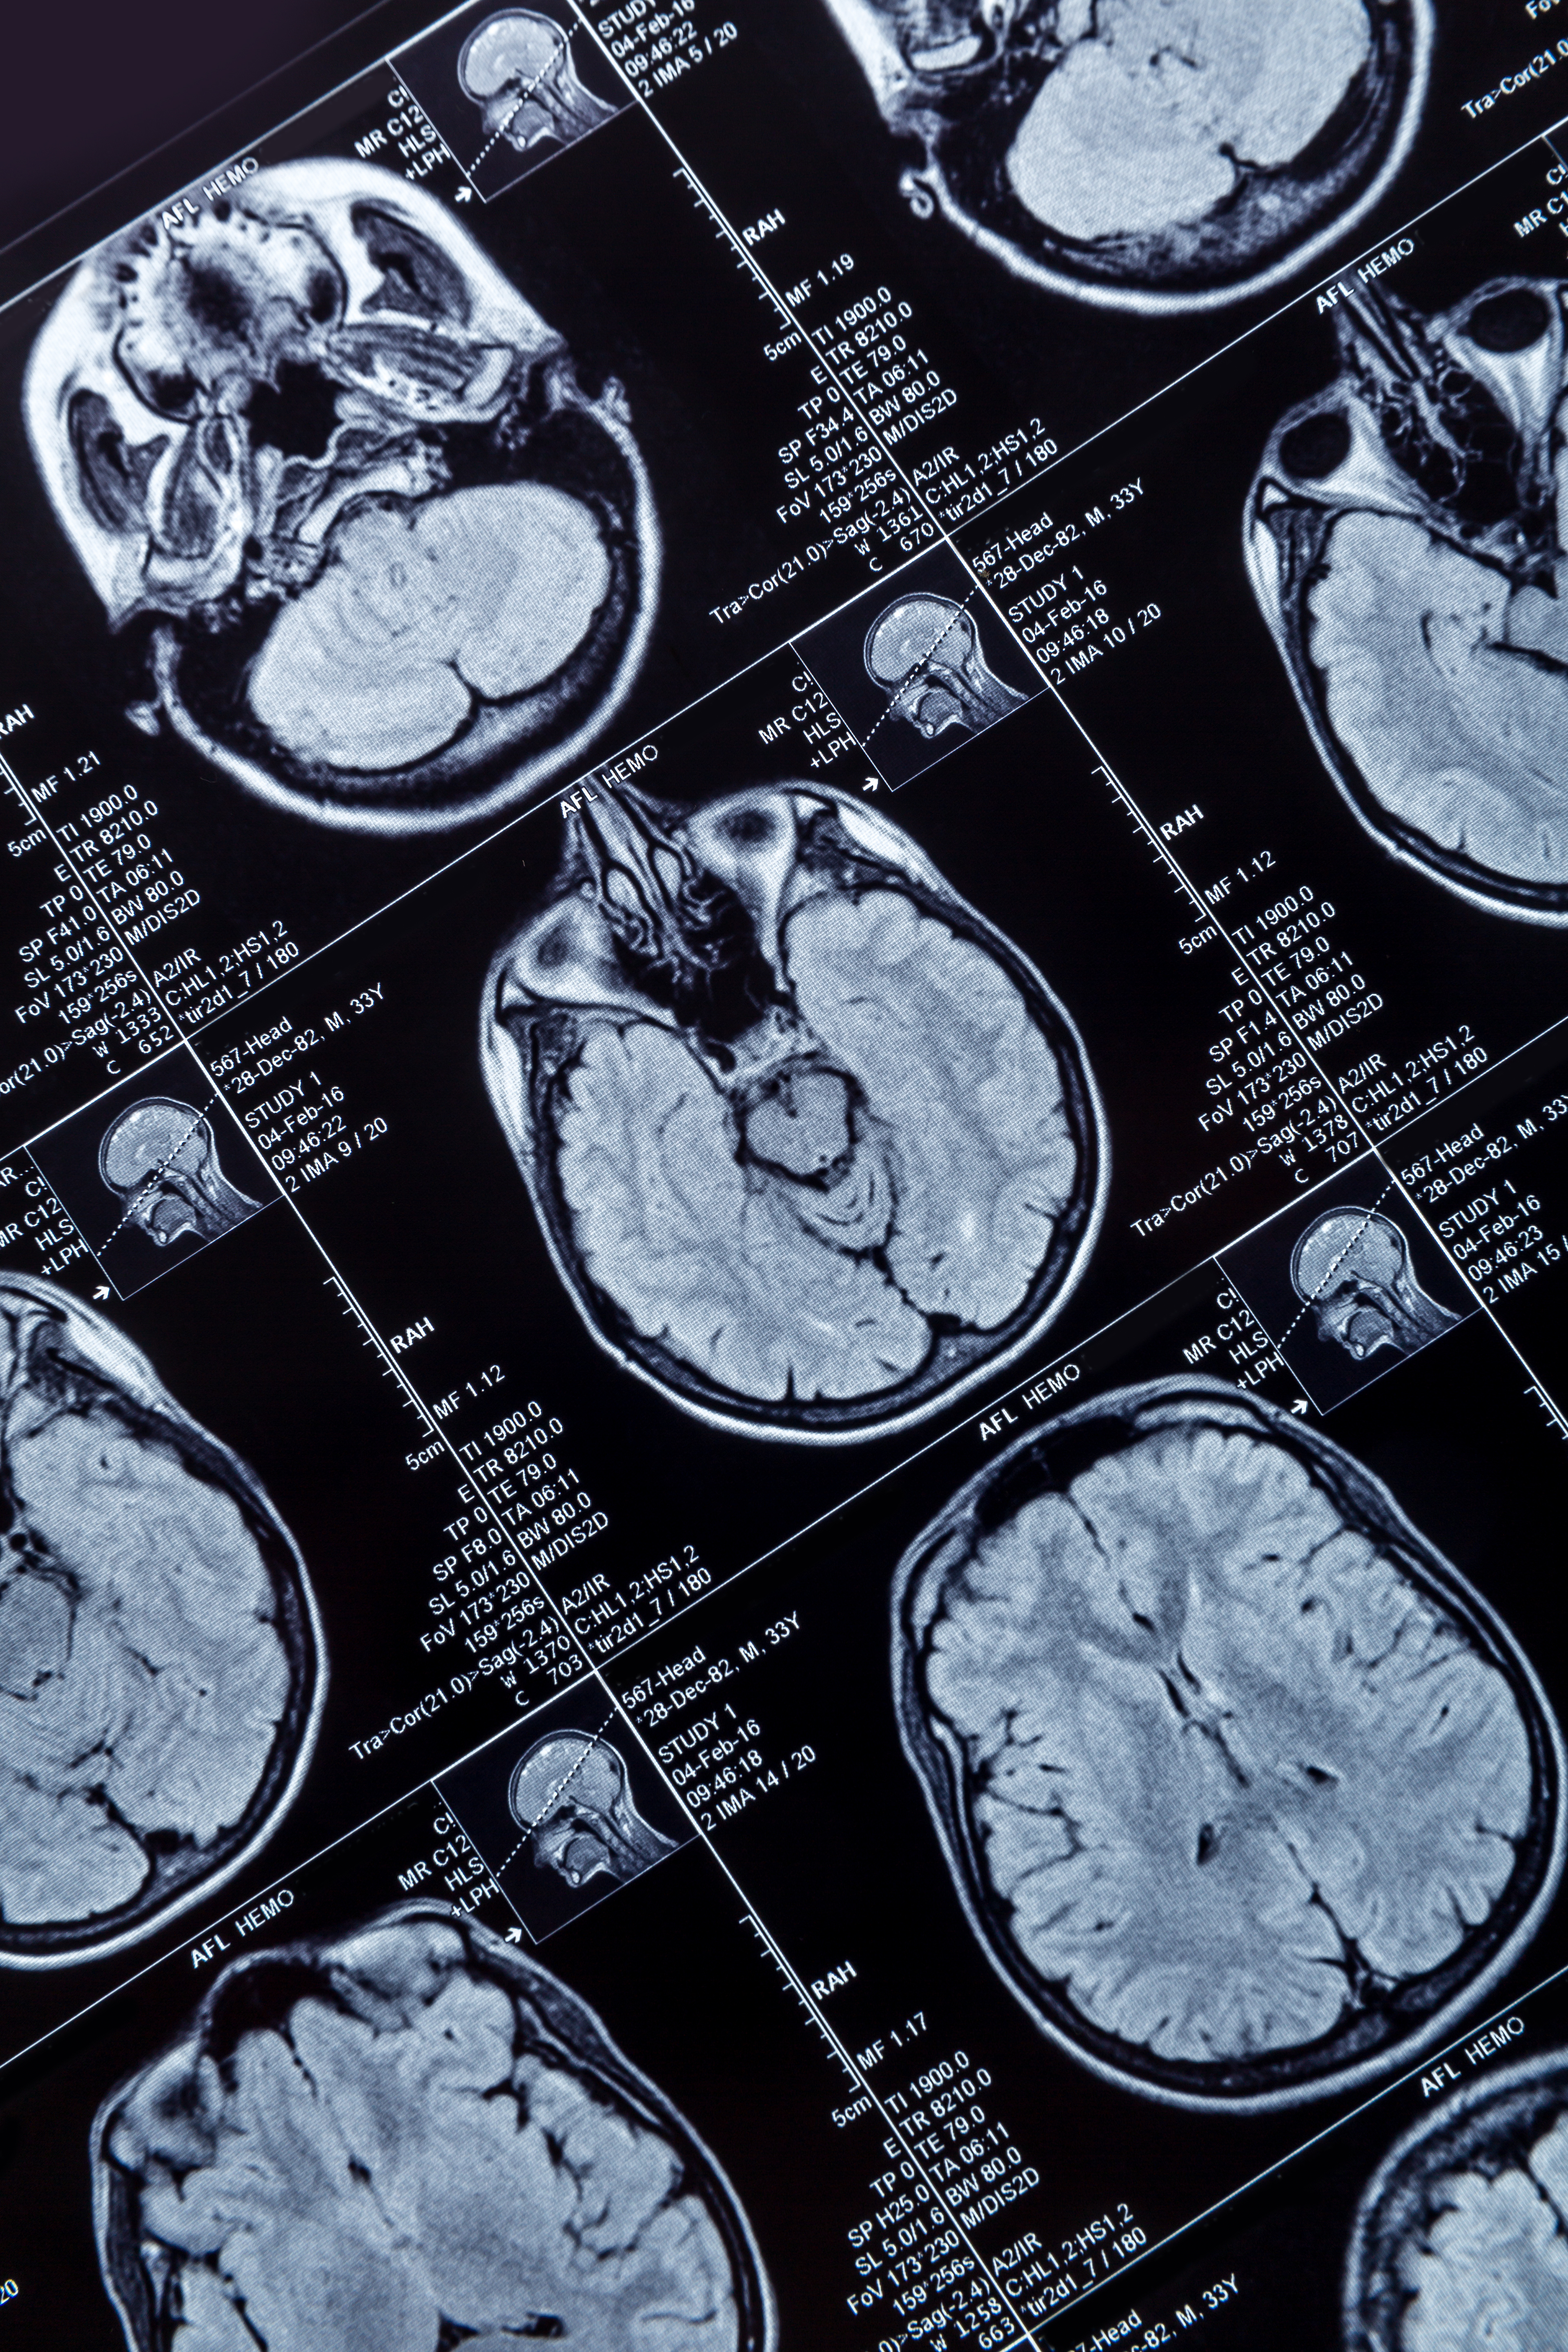

Clear cell chondrosarcoma can be seen in the left femoral head (arrow in a), and chondrosarcoma is visible in the left ilium (arrow in b and c). All figures courtesy of Dr. Rajesh Botchu.